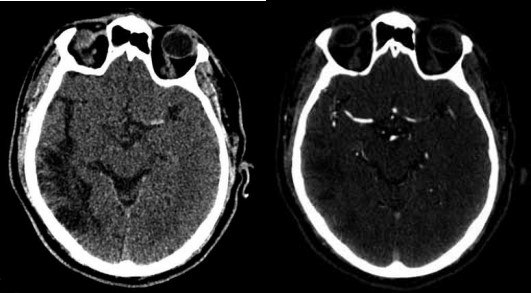

Paciente do sexo masculino, de 65 anos, foi trazido ao pronto-socorro com início súbito de afasia e hemiplegia direita há 4 horas. No exame clínico, apresentado NIHSS de 20. A tomografia computadorizada (TC) de crânios realizada não mostrou sinais de hemorragia intracraniana, mas evidenciou hipodensidade corticossubcortical no território da artéria cerebral média esquerda, com classificação ASPECTS de 8.

Considerando o relato, assinale a alternativa correta em relação ao achado das imagens a seguir:

(Arquivo pessoal; imagem usada com autorização)